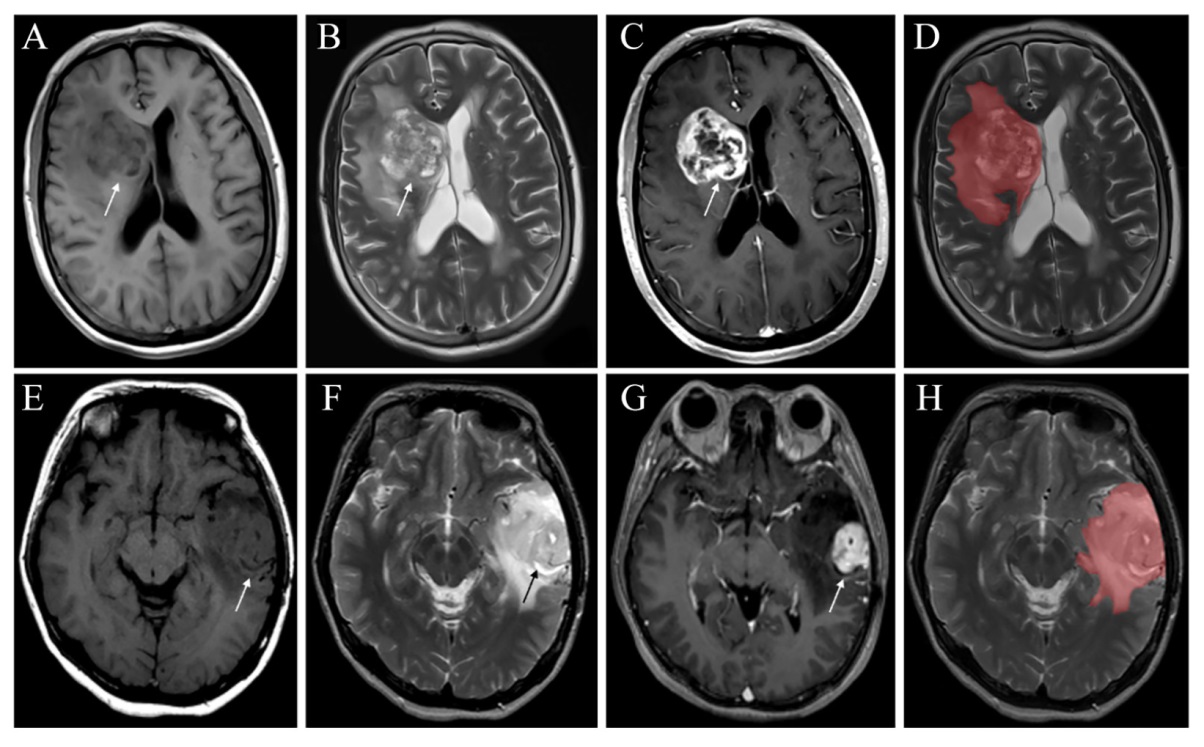

图1 一例胶质母细胞瘤及弥漫性星形细胞瘤患者的MRI图像及ROI勾画注:A~D为胶质母细胞瘤,IDH野生型,患者男,68岁。A~C分别为T1WI、T2WI及T1WI增强,病灶位于右侧侧脑室旁,呈长T1WI长T2WI混杂信号,边界欠清,周围脑实质水肿明显,增强扫描可见明显环形强化。D为以轴向T2WI图像为基础,在每个层面上勾画ROI,覆盖整个肿瘤(包括坏死、囊变区)及其瘤周水肿区域。E~H为弥漫性星形细胞瘤,IDH突变型,患者男,72岁。E~G分别为T1WI、T2WI及T1WI增强,病灶位于左侧颞叶,与胶质母细胞瘤表现相似,肉眼难以区分。H为ROI勾画方法,与D一致。 Figure 1 MRI images and ROI delineation of a patient with glioblastoma and diffuse astrocytoma |